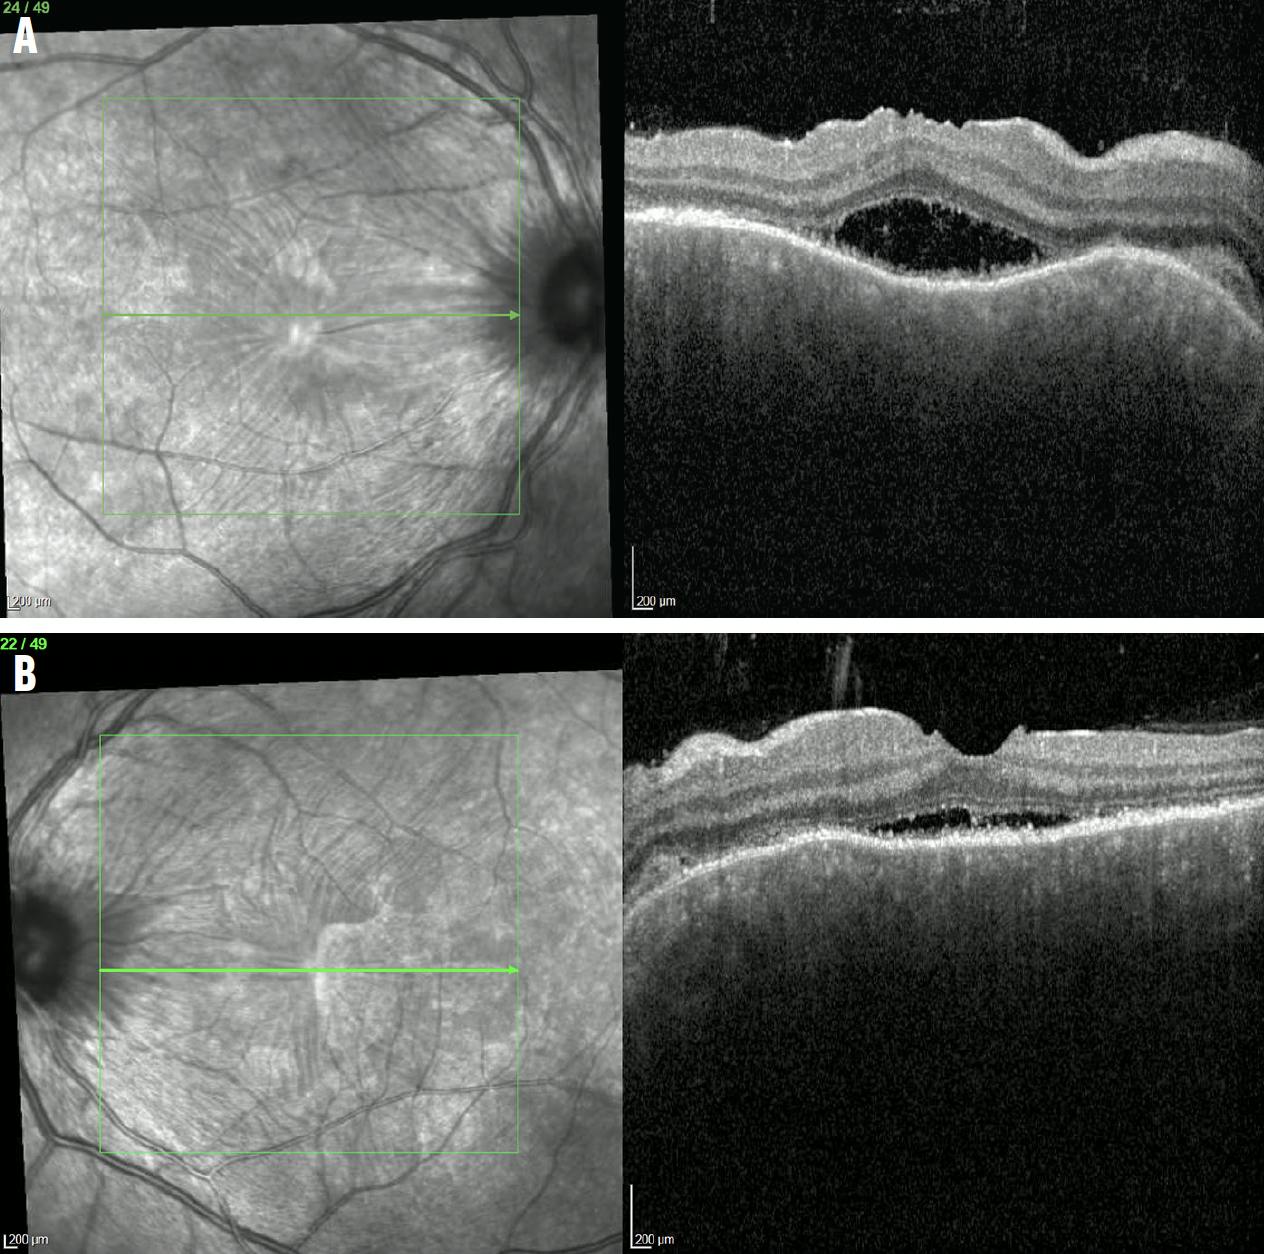

<p>Figure 6. OCT imaging of the macula of the right (A) and left (B) eye showed improvement of the subretinal fluid.</p>

Figure 6. OCT imaging of the macula of the right (A) and left (B) eye showed improvement of the subretinal fluid.

At the 1-week follow-up, she reported improvement of her eye pain and headaches and was afebrile. Although her vision was much better, she noted that it was still blurry and that lines looked wavy. Her fundoscopic examination showed that the retinal detachments had resolved (Figure 5). OCT of the macula showed mild subretinal fluid bilaterally that had dramatically improved since the last visit (Figure 6).